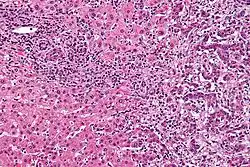

| Micrograph of an intrahepatic cholangiocarcinoma (right of image) adjacent to normal liver cells (left of image). H&E stain. | |

Histologically, cholangiocarcinomas may vary from undifferentiated to well-differentiated. They are often surrounded by a brisk fibrotic or desmoplastic tissue response; in the presence of extensive fibrosis, it can be difficult to distinguish well-differentiated cholangiocarcinoma from normal reactive epithelium. There is no entirely specific immunohistochemical stain that can distinguish malignant from benign biliary ductal tissue, although staining for cytokeratins, carcinoembryonic antigen, and mucins may aid in diagnosis.[47] Most tumors (>90%) are adenocarcinomas.[48]

Pathology

Histologically, cholangiocarcinomas are classically well to moderately differentiated adenocarcinomas. Immunohistochemistry is useful in the diagnosis and may be used to help differentiate a cholangiocarcinoma from hepatocellular carcinoma and metastasis of other gastrointestinal tumors.[66] Cytological scrapings are often nondiagnostic,[67] as these tumors typically have a desmoplastic stroma and, therefore, do not release diagnostic tumor cells with scrapings.